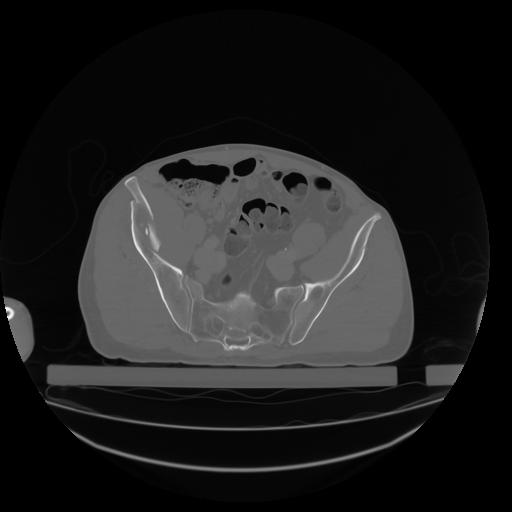

27 CUERPO,CE,Axial,3.0,CUERPO,,